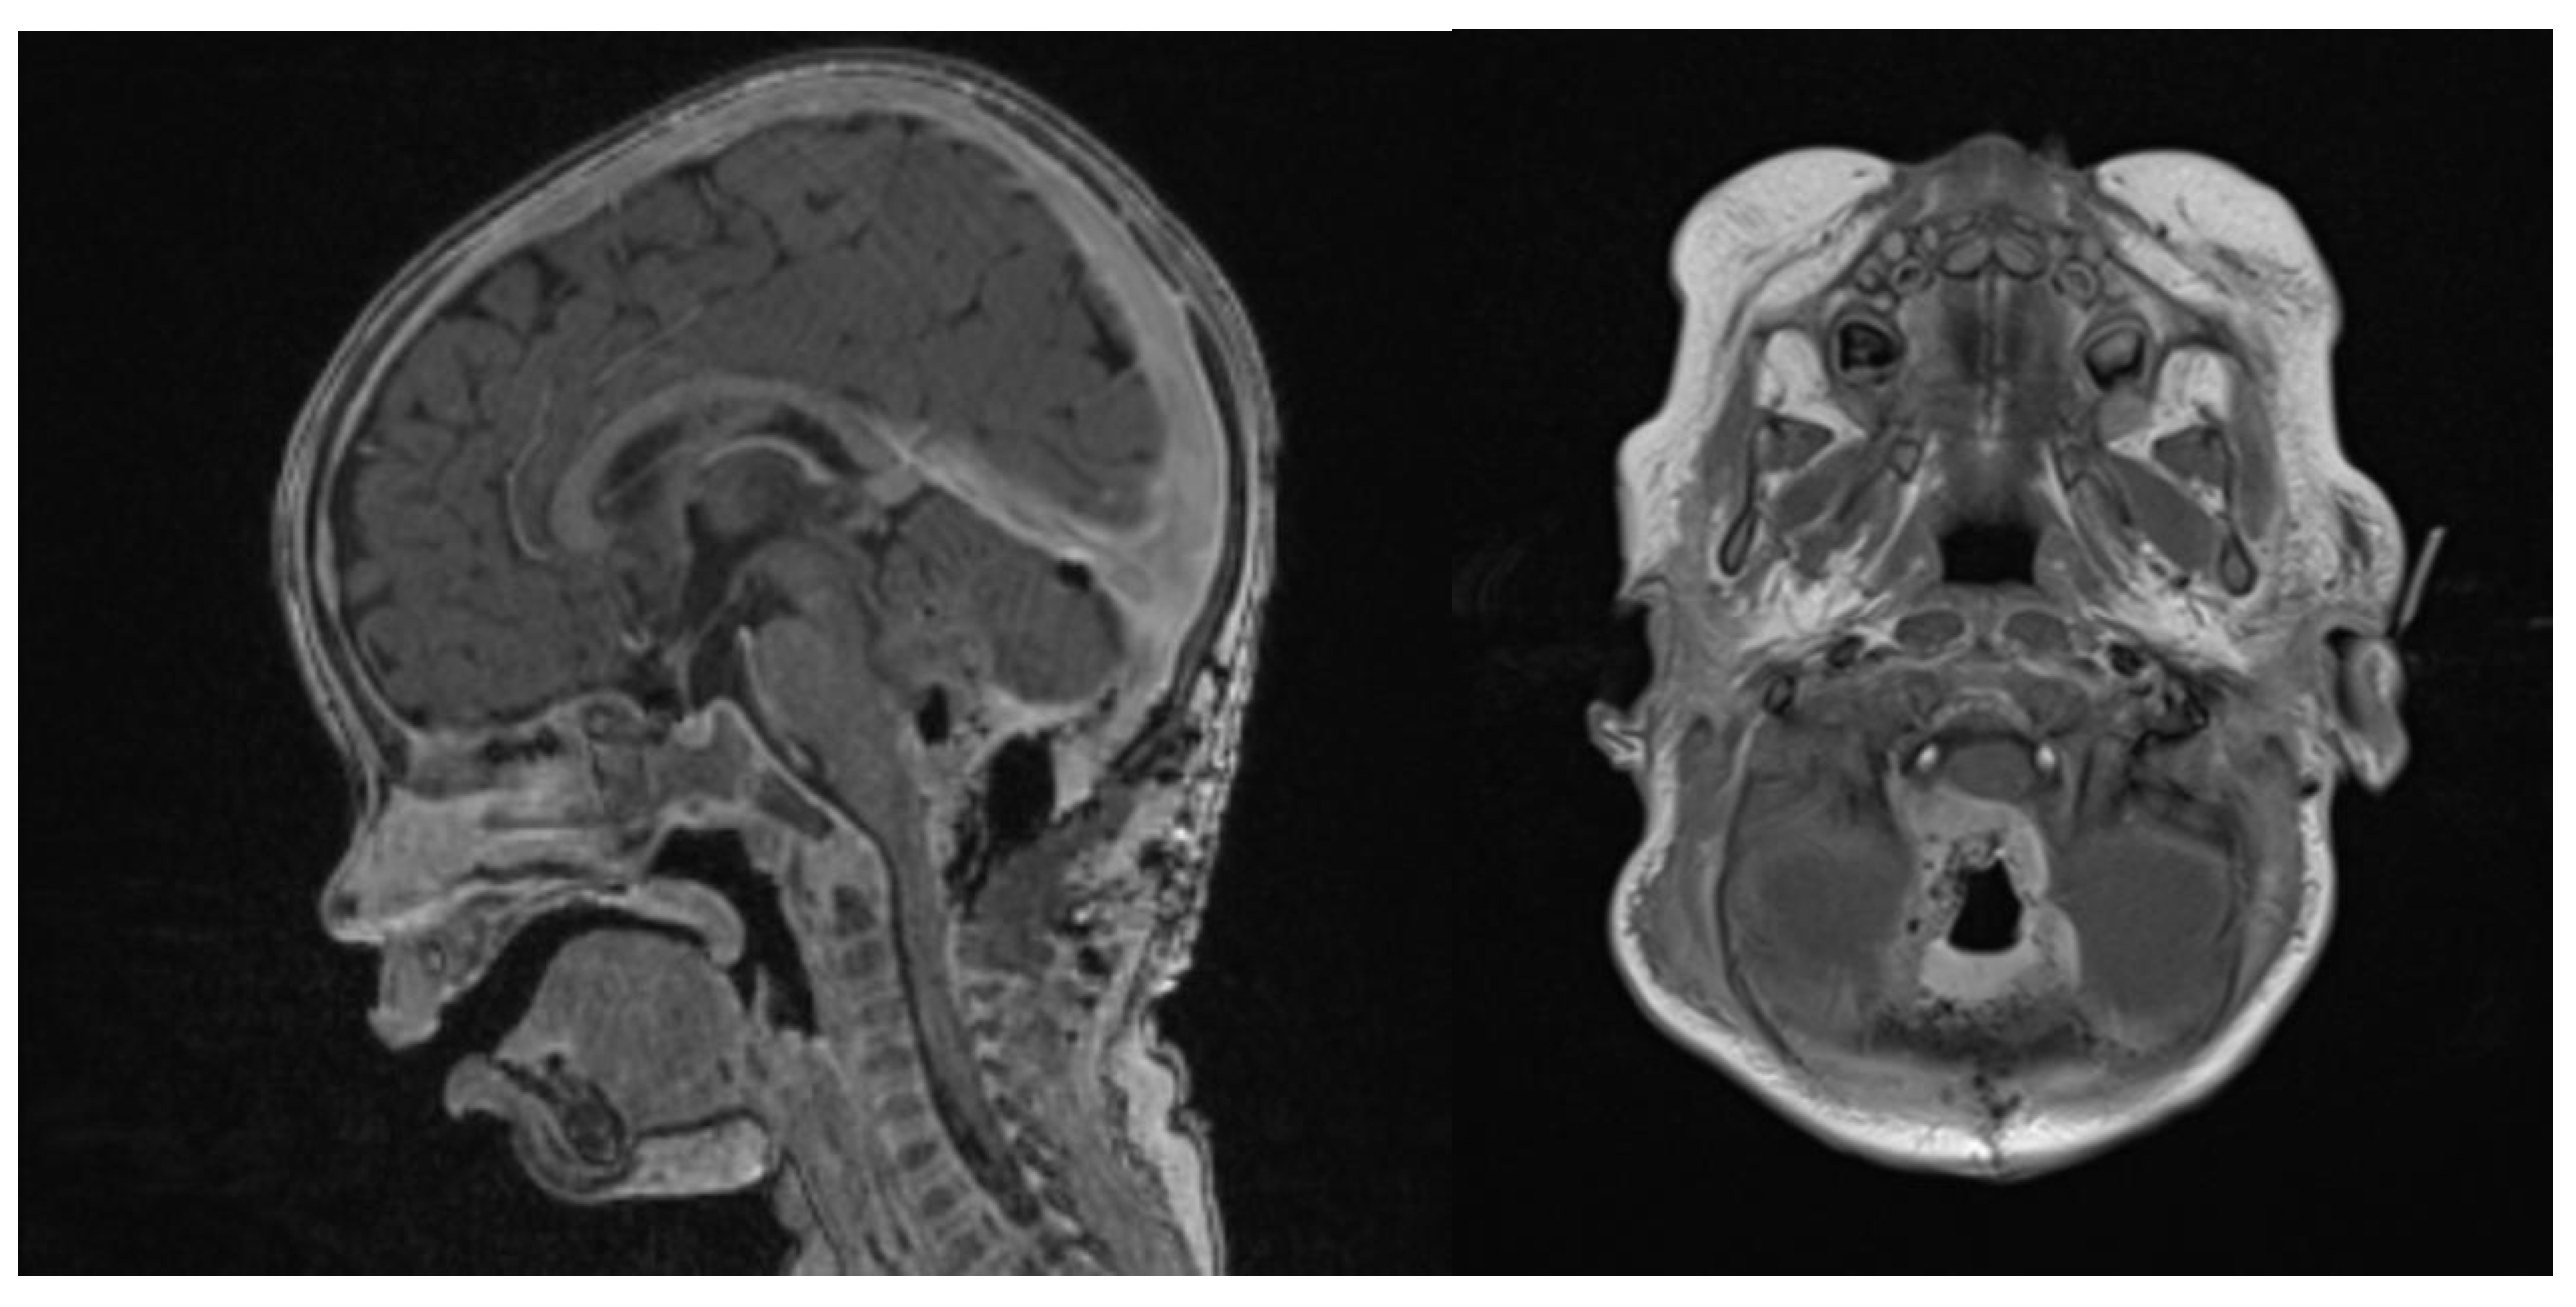

Clinical examination did not show any anterior fontanel bulging nor trismus. Whole brain and spine magnetic resonance imaging (MRI) was performed, showing a heterogeneous cystic-hemorrhagic lesion, partially calcified, in the posterior fossa, Measuring 46 × 34 × 49 mm and obstructing the IV ventricle and right Luschka foramen (Figure 2).

Figure 2.

Sagittal and axial gadolinium T1 MR sequence showing the exophytic mass occluding CSF diversion at the IV ventricle, compressing the brainstem and adjacent right cerebellar hemisphere.